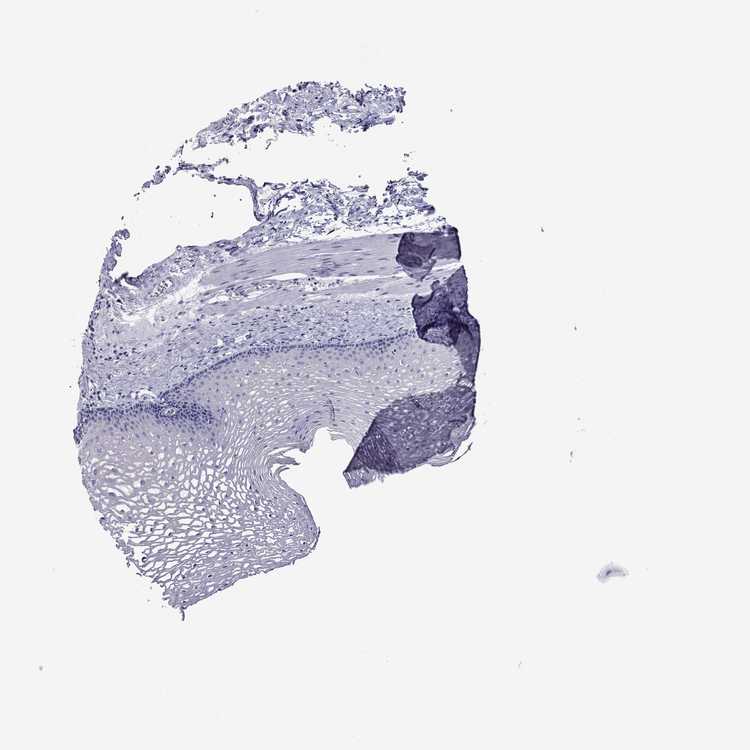

Information about each individual sample is listed below, including gender, age, a tissue section image and estimated fractions of cell types. nTPM (normalized transcripts per million) values give a quantification of the gene abundance which is comparable between different genes and samples.

Female, age 70

Esophagus sample 130

nTPM: 0

Cell types%

Squamous epithelial cells:

35

Smooth muscle cells:

15

Skeletal muscle cells:

5

Other cell types:

45